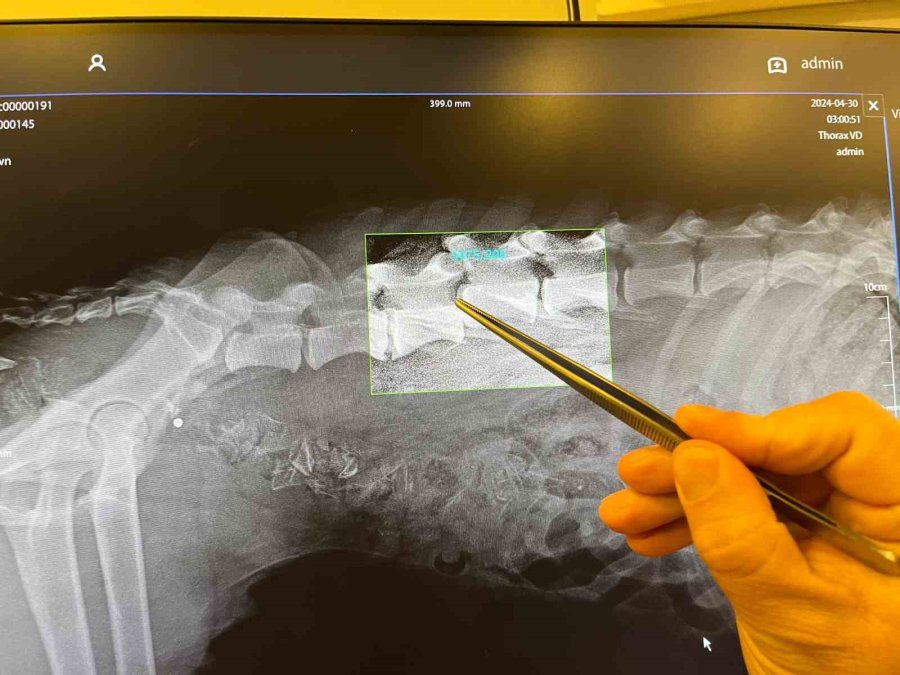

Geçtiğimiz günlerde Mihalıççık ilçesine bağlı Sazak Mahallesi yakınlarında hayvanseverler bir köpeğin acı çektiğini fark etti. Araçlarını kenara çekerek yol kenarında bulunan köpeğin yanına giden vatandaşlar, talihsiz hayvanın arka ayaklarını kullanamadığı için yürüyemediğini fark etti. Kent merkezine yaklaşık 150 kilometre uzaklıkta olan mahalleden köpeği araçlarına alan vatandaşlar, MANCAHANE Başkanı Nesrin Çiçek'e haber vererek, yaralı hayvanı özel bir veteriner kliniğine getirdi. Burada filmi çekilen köpeğin omurgasının bazı bölümlerinde kırık olduğu, buna bağlı olarak yürüyemediği belirlendi.

Köpeğin durumu hakkında detaylı bilgi veren Veteriner Hekim Evren Fatih Mumcu, "Köpeğimiz dişi ve yaklaşık 1 buçuk yaşında. Bel omurlarının 5. ve 4 omurlarında bir kırığımız var. Buraya bir operasyon yapacağız. Ama bu operasyonlar şans operasyonudur. İnşallah yürütebiliriz. Muhtemelen bir araç çarpmış. Tam arkasından vurmuş. Bel omurları ikiye ayrılmış. Fakat şöyle söyleyeyim, yüzde 80 iyileşme ihtimali var. Durumu çok kötü değil. Ama omurga cerrahisi zor bir operasyon. Getirilmeseydi arka tarafları sürüyerek tamamen kötürüm kalırdı ve sürüye sürüye kasları tamamen dışarı çıkarıp ölürdü" dedi.